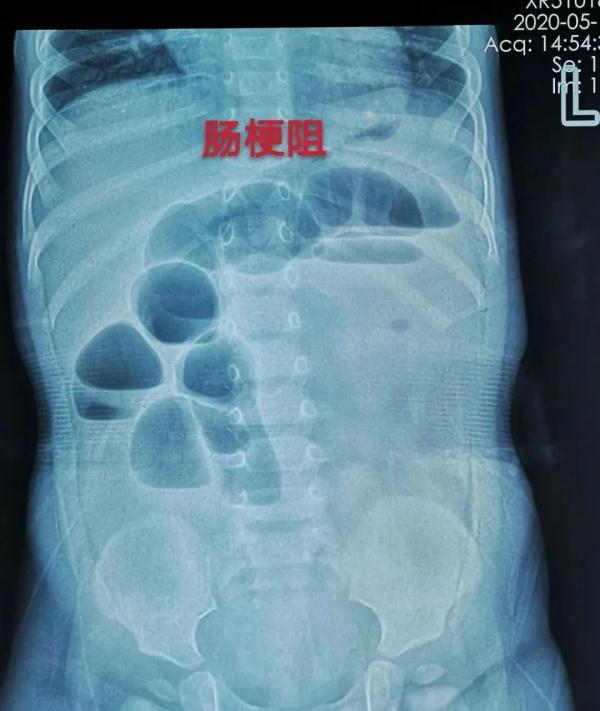

佳佳(化名)近两天出现精神差、哭闹、不想吃东西、频繁恶心呕吐、腹胀、不排大便的情况,在当地数家医院就诊考虑肠梗阻,但查不出梗阻的原因。于是,心急如焚的家长带着佳佳来到郑州的大医院做进一步检查。

医生凭借多年从医经验,做出诊断:孩子的肠梗阻是由消化道异物引起的。

2. 进入消化系统中的海绵宝宝还会不断吸水膨胀,影响肠胃的正常蠕动和消化功能,如果无法及时排出可引发感染、电解质紊乱、肠梗阻甚至肠道穿孔和坏死。